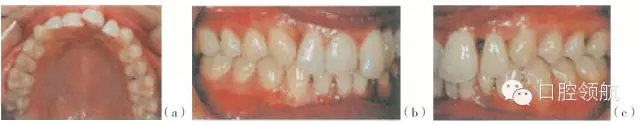

圖29.4 (a~c)有局限型侵襲性牙周炎病史的28歲的女性患者(不吸煙),之前進(jìn)行過牙周治療,左上中切牙及左下側(cè)切牙有炎癥。左下中切牙已有移位,不在牙弓的正?;【€內(nèi),出現(xiàn)傾斜及旋轉(zhuǎn)

圖29.5 (a,d)圖29.4患者的X線片,咬合面的X線片顯示上頜第一磨牙遠(yuǎn)中及下頜左側(cè)

第二磨牙,有齦下牙石和牙槽骨吸收。(b,c,e,f)根尖片顯示右上側(cè)切牙,左上中切

牙及側(cè)切牙,左下側(cè)切牙有齦下牙石及牙槽骨吸收